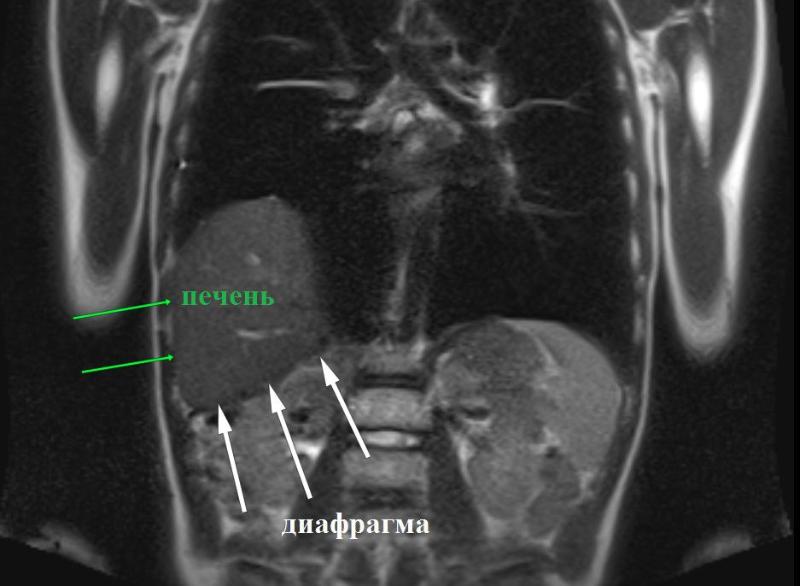

Диафрагмальная грыжа встречается примерно у 3 из 10 тысяч новорожденных. Грыжи могут быть как врожденными, так и приобретенными вследствие перенесенных инфекций. В данном случае врачи определили врожденный характер патологии. Показанием к операции стало неестественное состояние купола диафрагмы. Хирурги ДРКБ выполнили торакоскопическую пластику диафрагмы, минимизировав травматичность вмешательства, поскольку операция была проведена без разрезов.